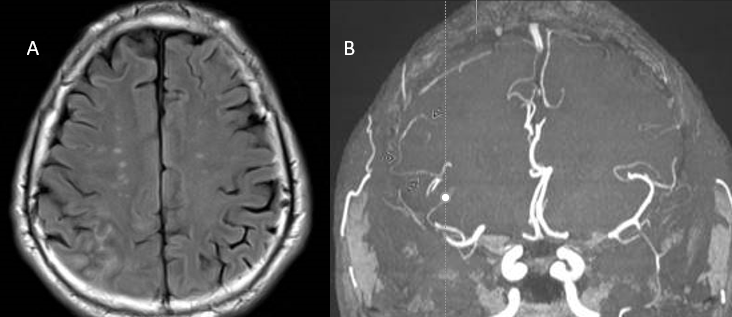

Magnetic resonance imaging (MRI) of brain and spine with and without contrast is the modality of choice in initial neuroimaging of PACNS. Unfortunately, the neuroimaging findings in PACNS are nonspecific and variable, and depend on which arteries or veins are affected. The most commonly seen abnormalities are infarcts in both cortical and subcortical regions, which are frequently multiple and bilateral.[1][2][3][6] In contrast, children are more likely to have unilateral, white matter lesions.[5] Other MRI findings seen in PACNS include gadolinium-enhancing lesions, intracranial hemorrhage as a consequence of inflammation, and mass lesions that may appear to be tumors.[1][2][3]

Cerebral angiography can reveal vascular abnormalities suggestive of vasculitis and can be especially useful when biopsy is not possible. However, angiography has variable sensitivity and variations in vessel caliber and shape are not specific for vasculitis.[2][3] Many other conditions such as vasospasm, atherosclerosis, and infections can produce the same appearance on angiogram as PACNS.[1] Characteristic vasculitic patterns for PACNS include “beaded” vessels (alternating segments of stenosis and normal or dilated lumen), occlusions, and collateral circulation..[1][2][3] Both small and large vessels can be affected, departing from the convention that vasculitides only affect one type of vessel size.